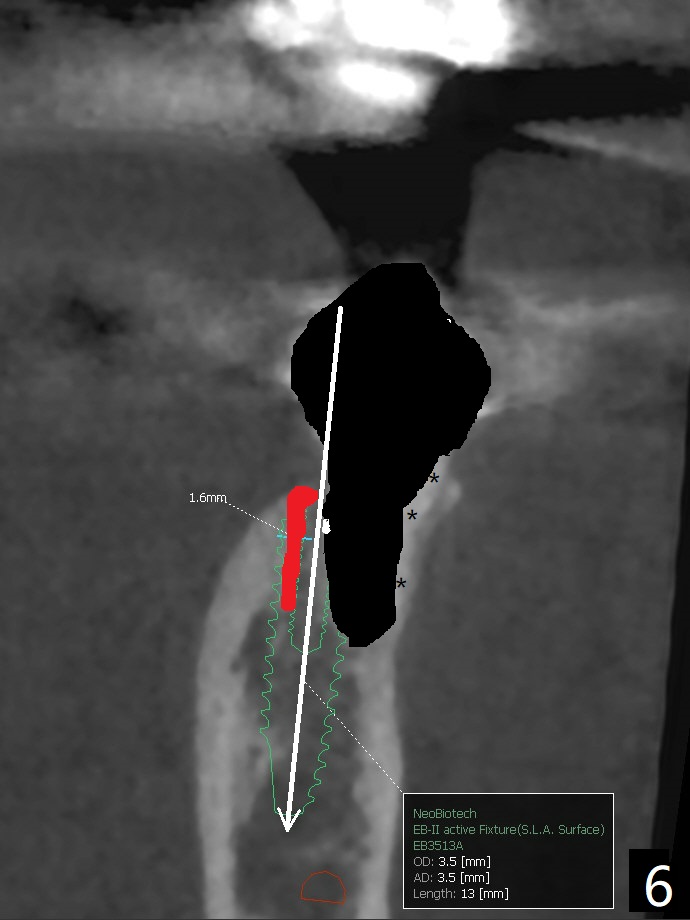

A 53-year-old woman develops an abscess lingual to the tooth #20 before #19 final restoration. Reanalysis of CT taken 5 months earlier shows the thin buccal plate (Fig.1 B). A 3.5x13 mm bone-level/3.5x17 mm tissue-level implant should be lingually placed (Fig.2,3). Socket shield will be performed (Fig.4 *); the lingual cortex removed with Lindamann bur (red) for ~1.6 mm. Initial osteotomy will be conducted in the lingual wall of the socket coronally (Fig.5 white arrow); after penetration, the initial drill will change the trajectory (Fig.6).